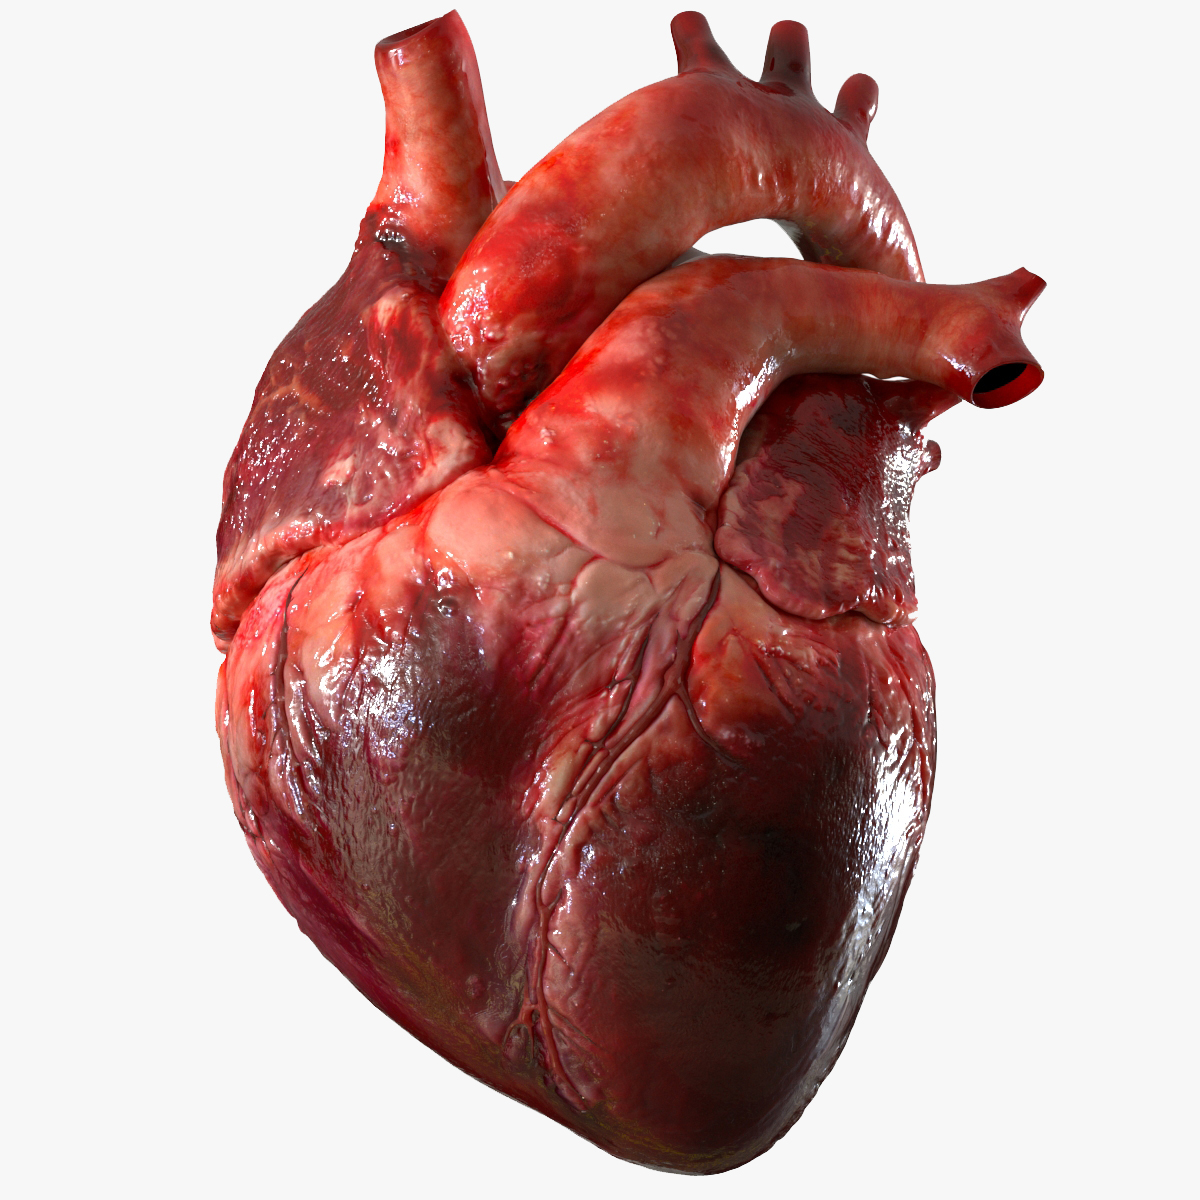

Realistic Human Heart 3D model | CGTrader  anatomy human heart 3d c4d

3D human heart - TurboSquid 1737445  How to Draw a Human Heart - Really Easy Drawing Tutorial

Image of Human Heart 3D Illustration | Stock Image MXI28575  The human heart by SkarlettFury on DeviantArt | Human heart drawing, Heart drawing, Heart art